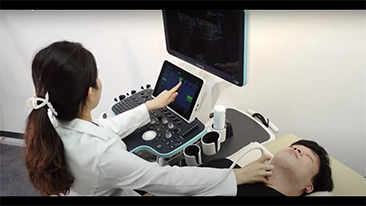

Mindray Resona Genel G?rĂŒntĂŒleme ??zĂŒmleri, kapsaml? alt b?lĂŒm uygulama problar? ve verimli klinik uygulama ara?lar? arac?l???yla, klinisyenlerin daha do?ru ve verimli tan? ve tedavi sonu?lar? elde etmesine yard?mc? olur.

Genel G?rĂŒntĂŒleme ?rĂŒnleri